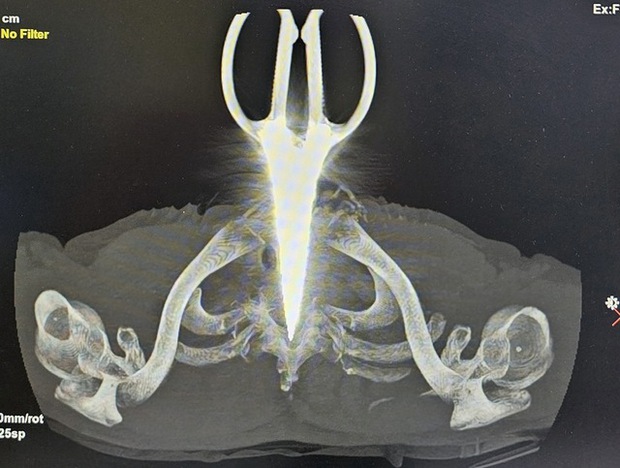

Khám phá câu chuyện đầy kỳ diệu về người đàn ông mù 2 mắt đã tự lấy kéo đâm vào bụng và ngực của mình, nhưng được cứu sống thông qua một ca phẫu thuật phức tạp và thành công tại Bệnh viện Đa khoa Trung ương Cần Thơ.

Người đàn ông mù 2 mắt tự lấy kéo đâm vào bụng và cổ - Ảnh 2.